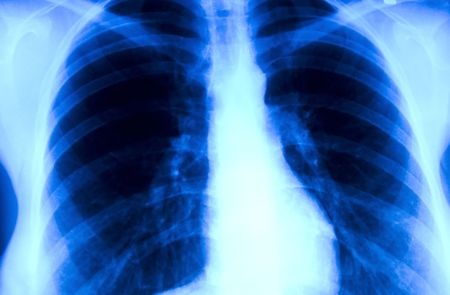

24 marca przypadł Światowy Dzień Walki z Gruźlicą

Gruźlica jest chorobą zakaźną, wywołaną przez prątki kwasooporne z grupy Mycobacterium tuberculosis complex – M. tuberculosis, M. bovis i M.

africanum. Światowy dzień walki z tą chorobą ustanowiono 24 marca w celu upamiętnienia wydarzenia z 1882 roku, kiedy Robert Koch ogłosił swoje odkrycie.Mimo postępu w zmiejszaniu liczby zachorowań, gruźlica jest nadal groźna. Według najnowszego raportu Światowej Organizacji Zdrowia

(WHO) i Europejskiego Centrum Kontroli Chorób (ECDC),w latach 2011-2015 w Europie liczba zachorowań na gruźlicę spadła o 4,3 proc., a liczba zgonów – o 8,5 proc. Jednocześnie o 40 proc. wzrosła liczba przypadków tej choroby u osób z wirusem HIV.